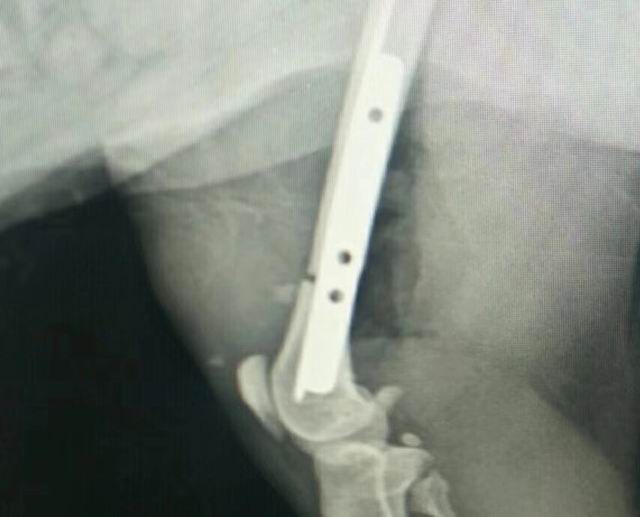

一例貓咪骨折/內(nèi)固定術(shù)

藍(lán)白,2歲,外固定失敗轉(zhuǎn)于我院,實(shí)施骨折內(nèi)固定,術(shù)前體檢+進(jìn)口麻藥+手術(shù)順利(ok),住院護(hù)理中……急主人所急,想主人所想,致力于寵物健康,洛陽狗博仕寵物醫(yī)院